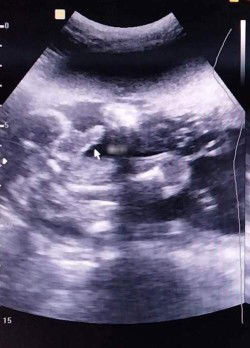

Boy or Girl?

Mga mommies ano pong gender ng baby ko thank you sa mga sasagot

Kung yung naka arrow is yung genital niya, mukhang boy.